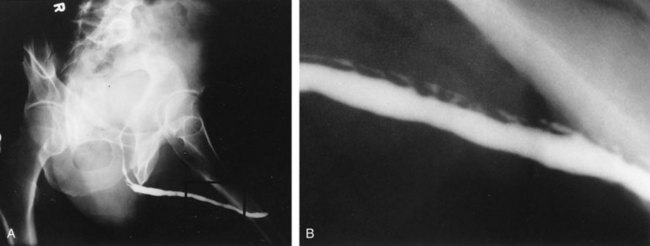

In young patients with severe meatal stenosis, surgery is indicated. Because patients with long-standing meatal stenosis often have severe proximal urethral stricture disease, retrograde urethrography should be performed before the initiation of therapy. The etiology of stricture disease associated with LS is unclear. Possible causes include iatrogenic stricture resulting from repeated instrumentation and pressure voiding associated with meatal stenosis causing secondary intravasation of urine into the glans Littre (Fig. 36–14). In cases of early LS with only meatal involvement resulting in stenosis of the fossa navicularis, prompt reconstruction seems to be successful in the long term and seems to avoid the sequelae of panurethral stricture disease. Most surgeons now believe that because LS is a disease of genital skin, better tissue for reconstruction is the oral mucosa, and techniques are discussed later (Mundy, 1994; Bracka, 1999). Long-standing cases with a long length of urethral stricture are amenable to techniques of reconstruction but are very challenging. It is becoming clear that except in the case of urethral stricture disease confined only to the meatus and fossa navicularis, staged oral graft reconstruction, at least in the short to mid term, seems to provide superior durable results. This may also be the case in cases confined to the meatus and fossa navicularis, because a recent analysis of patients reconstructed with the ventral transverse skin island technique showed a 50% recurrence rate even in those patients. The weakness of that analysis, is that the data did not include biopsy proof that all patients had LS (Virasoro et al, 2007). We also are seeing more and more patients who present with a buried penis. This phenomenon occurs when the skin of the penile shaft has been lost because of severe inflammation, and the penis is trapped in the penopubic and scrotal area. These patients are often profoundly overweight, and many are diabetic; they have often had prior surgical procedures. Their management is complex and ultimately determined by their desire and need for functional reconstruction. In some patients with severe urethral stricture disease, we have completely reconstructed the urethra; in others, we have simply performed a perineal urethrostomy. Perineal urethrostomy is usually technically straightforward, because the rule in most patients with lichen sclerosus is to spare the proximal anterior urethra. We have proposed that, in many cases, the sparing of the proximal anterior urethra demonstrates the distribution of the glands of Littre for a given patient. Younger patients have requested mobilization and release of the penis with placement of a split-thickness skin graft. However, because the inflammation involves the glans penis (which is not removed), the secondary inflammation may also involve the skin graft. Therefore lifelong monitoring of these patients for the secondary effects of inflammation is necessary.

Figure 36–14 A and B, Urethrogram in a patient with urethral stricture disease associated with lichen sclerosus–balanitis xerotica obliterans. It illustrates the intravasation of contrast material into the dilated glands of Littre during voiding.

(From Jordan GH. Management of membranous urethral strictures via the perineal approach. In: McAninch J, Carroll P, Jordan GH, editors. Traumatic and reconstructive urology. Philadelphia: WB Saunders; 1996.)